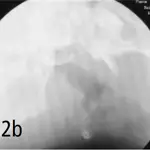

Fluoroscopic examination demonstrates thickening of the soft palate, without evidence of elongation, and thickening of the retropharyngeal tissues with near-total obliteration of the naso- and oropharyngeal air passages during inspiration. The patient's cervical trachea shows moderate variation in diameter during respiration. A cough could not be induced during this procedure.

Figure 3. Spot films from fluoroscopic study demonstrating maximal change in tracheal diameter that occurred in this dog. A cough could not be induced during this procedure.